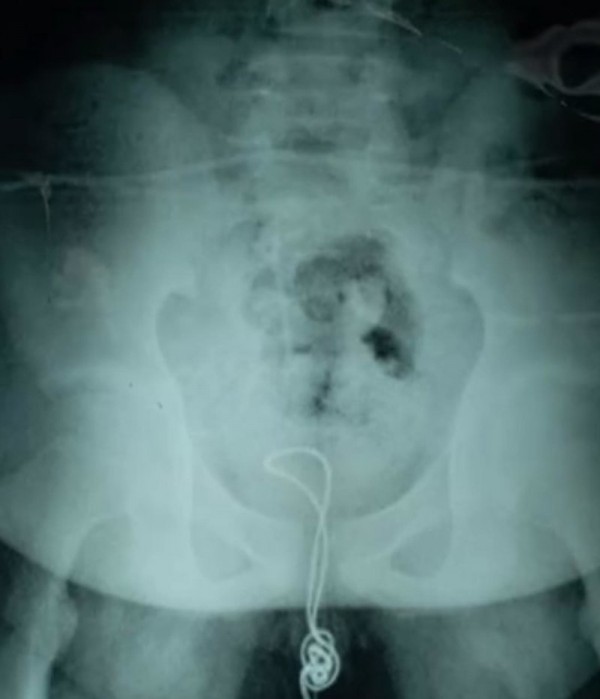

"Он отрезал один конец кабеля и вставил его в уретру, - рассказала доктор Лиянь о том, как парень засунул аксессуар себе в половой орган. - Кабель достиг его мочевого пузыря, где запутался и образовал узел, поэтому, когда он попытался его вытащить, тот застрял."

Когда же ситуация прояснилась, врачи взялись за работу. Доктор Сюй и её команда добрались до мочевого пузыря мальчика, распутали узел и затем через хирургический разрез удалили часть кабеля

Остаток шнура был вытащен через уретру. Сообщается, что подросток был выписан из больницы несколько дней назад, проведя в лечебном заведении приблизительно две недели.